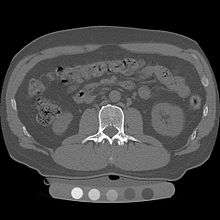

Dual use of CT images

Several studies have shown that bone density may be measured by QCT using CT images that were ordered for other purposes. Using pre-existing images, including CT colonography exams,[14] QCT allows for bone density screening without submitting the patient to any additional radiation exposure. The feasibility of using routine abdominal contrast-enhanced CT scans for the evaluation of bone density by QCT has also been demonstrated.[15]